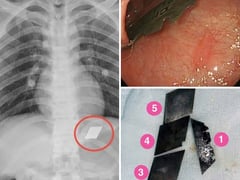

Hãi hùng một bệnh nhân "ngáo đá" ở TP HCM nuốt trọn bộ dao 5 món vào bụng

E kíp Bệnh viện đa khoa Bình Dương đã phẫu thuật lấy dao lam kẹt ở miệng thực quản, hạ họng và 4 mảnh dao rọc giấy trong dạ dày bệnh nhân "ngáo đá"